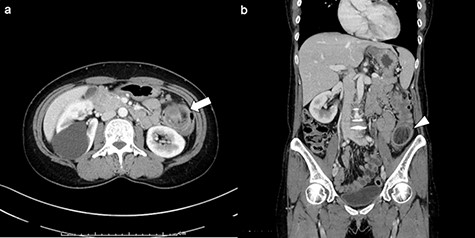

A 50-year-old woman visited a family hospital with complaints of left lower abdominal pain and bloody stool. She had no relevant past medical history or family history. She underwent colonoscopy, and a submucosal tumor was detected in her colon. She was referred to our hospital for further testing and treatment. Colonoscopy was performed, and an ulcerating submucosal tumor with necrosis at the surface was detected in the colon 40 cm from anal verge (Fig. 1). There were no other abnormal lesions in her colon. Histopathological examination of biopsy samples of the tumor comprised only exudate and no cellular components.

Colonoscopy findings: a submucosal tumor with ulceration and necrosis at the surface was detected in the colon 40 cm from anal verge. There were no other abnormal lesions in her colon.